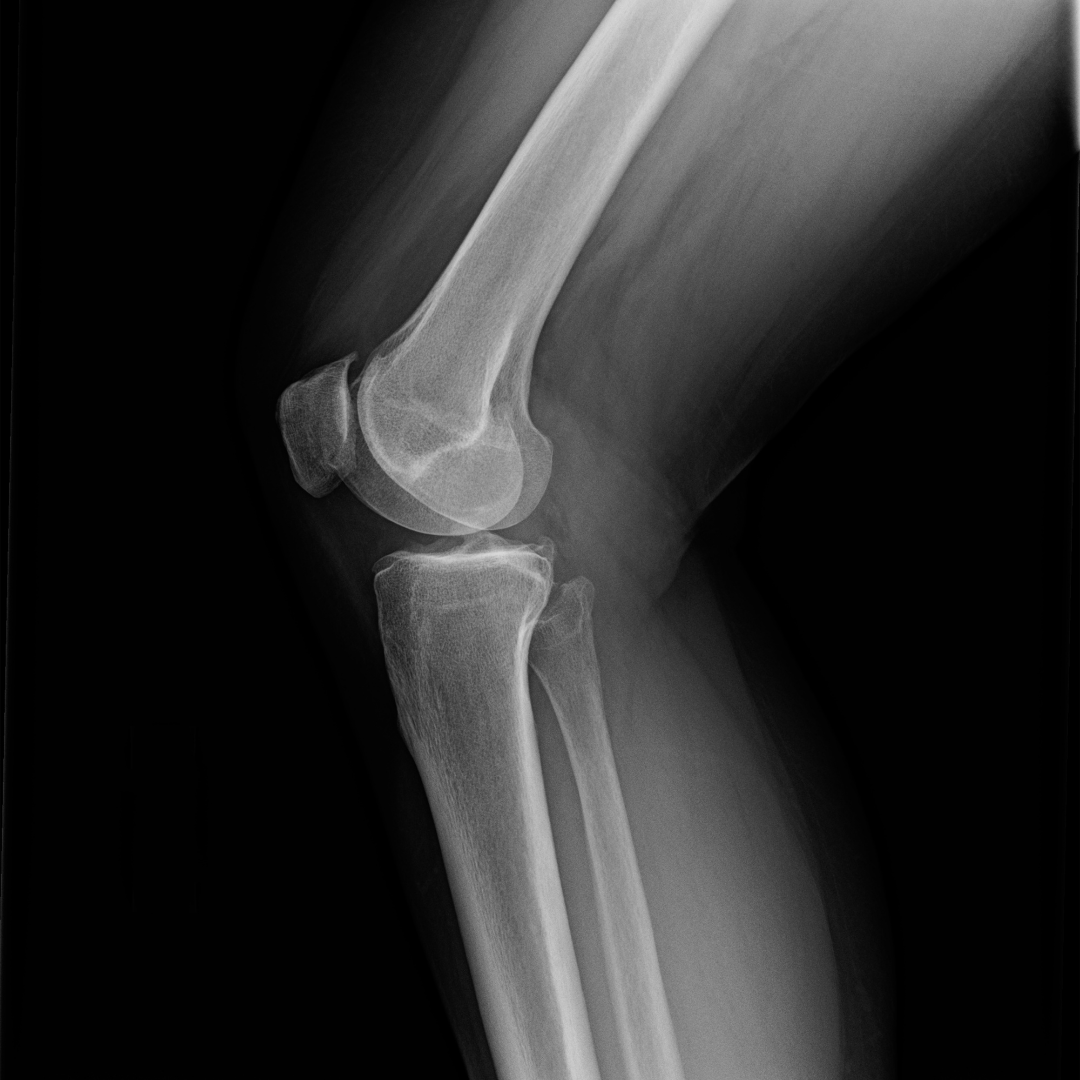

Bone structure

Not everybody can move the same way due to their bone structure, so we optimize and work with what you have to make it as efficient, smooth, and effortless as possible.